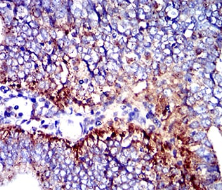

CD107b Mouse Monoclonal antibody[8E2F2]

IHC    1/200 - 1/1000